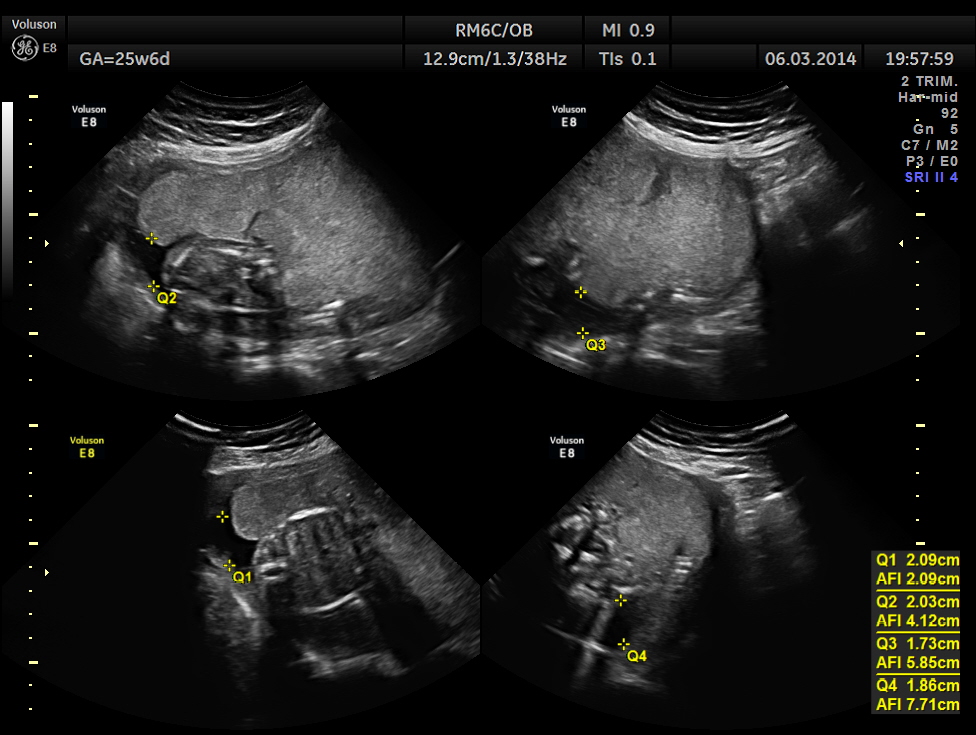

The GA was around 25 weeks , but the AUA was around 19 to 20 weeks. All parameters – BPD, HC, AC, FL are < 2.3 %tile and all other long bones are < 5.0 %tile.

Prominent placentomegaly seen .

Oligohydramnios seen.